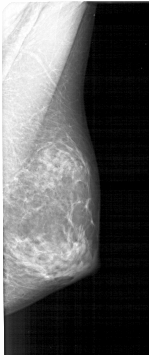

A_1379_1.RIGHT_CC

RIGHT_CC LINES 4531 PIXELS_PER_LINE 2191 BITS_PER_PIXEL 12 RESOLUTION 43.5 NON_OVERLAY